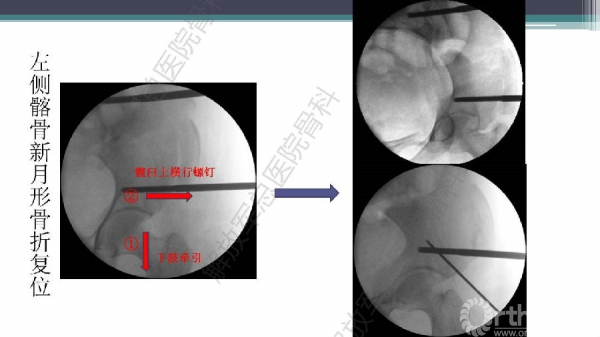

随着建筑和交通运输业的快速发展,合并骨盆、髋臼骨折多发伤、复合伤患者逐年增加,病死率和致残率都非常高。由于多发伤及复合伤、休克等往往不能在急性期对骨盆骨折进行确切复位及内固定,导致陈旧性骨盆骨折畸形愈合,从而产生一系列严重并发症,并且畸形矫正手术难度大、风险高、效果差。因此在抢救复苏后能不能尽早地、小切口甚至不切开、精确复位与固定骨盆骨折,防止陈旧性骨盆畸形愈合形成,成为广大骨科医生的挑战。解放军总医院创伤骨科在骨盆、髋臼骨折微创治疗方面做了一些工作,从微创理论探讨、到手术方法的改进,乃至钢板螺钉、微创复位器械等相继研发,形成了一系列的解决方案和配套内固定产品,为骨盆髋臼骨折的微创治疗奠定了基础。本幻灯则通过一例陈旧骨盆骨折畸形愈合的复杂治疗做引,通过介绍骨盆空间移位方式、透视特点、骨盆随意外架复位系统、复位原理以及1例典型病例的具体实施方案来综合、全面介绍我院微创骨盆髋臼骨折复位、固定新技术。